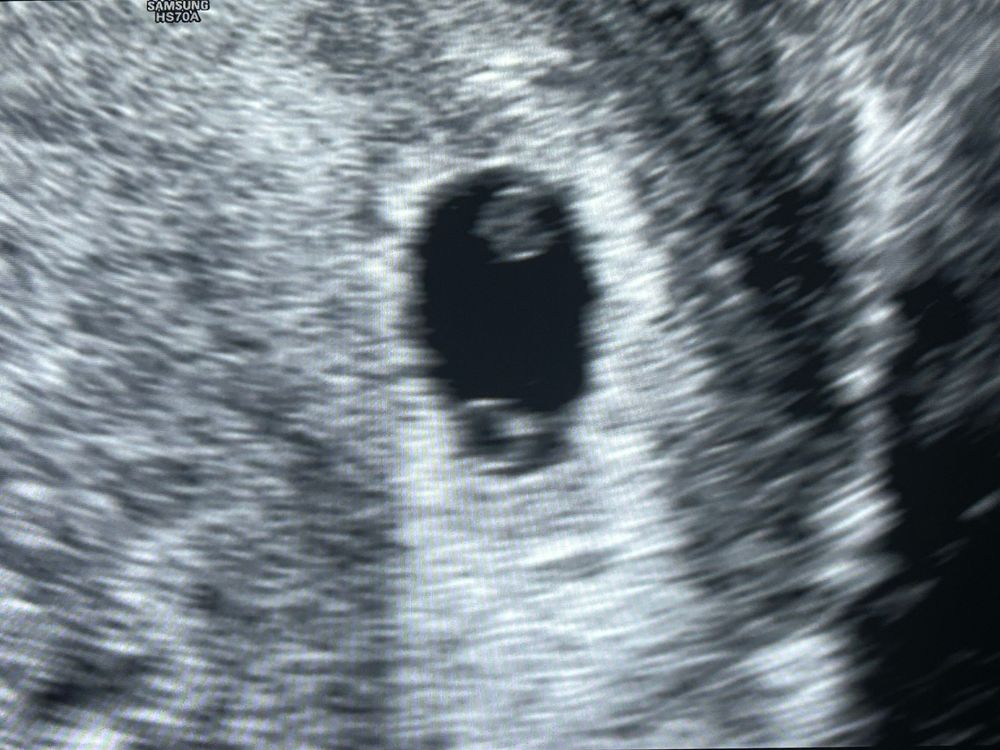

В одном плодном яйце 2 эмбриона..

Девочки расскажите пожалуйста может у кого так было.На 15 дпо была на узи,нашли пя 3,77 мм. Сегодня 26 дпо. Около 11 дней задержки. Я пошла на повторное узи,пя 13 мм и в нем 2 жм и два эмбриона с сердца биением. По узи поставила срок 6 недель. Я тут столько всего начиталась,что это моно двойня ,и выносить шансов очень мало.Госпади мне теперь так страшно. Может у кого была такая беременность, поделитесь пожалуйста историями